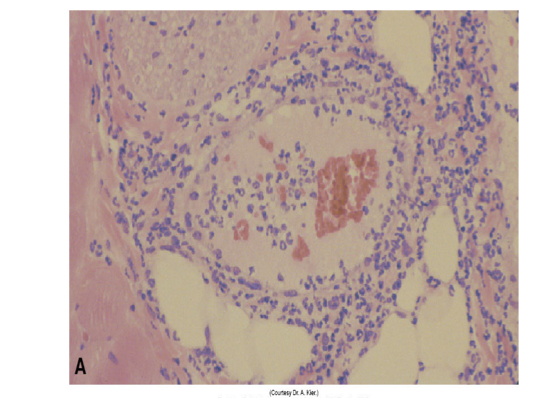

<p>whats this show</p>

arthus rxn in cat after vacc